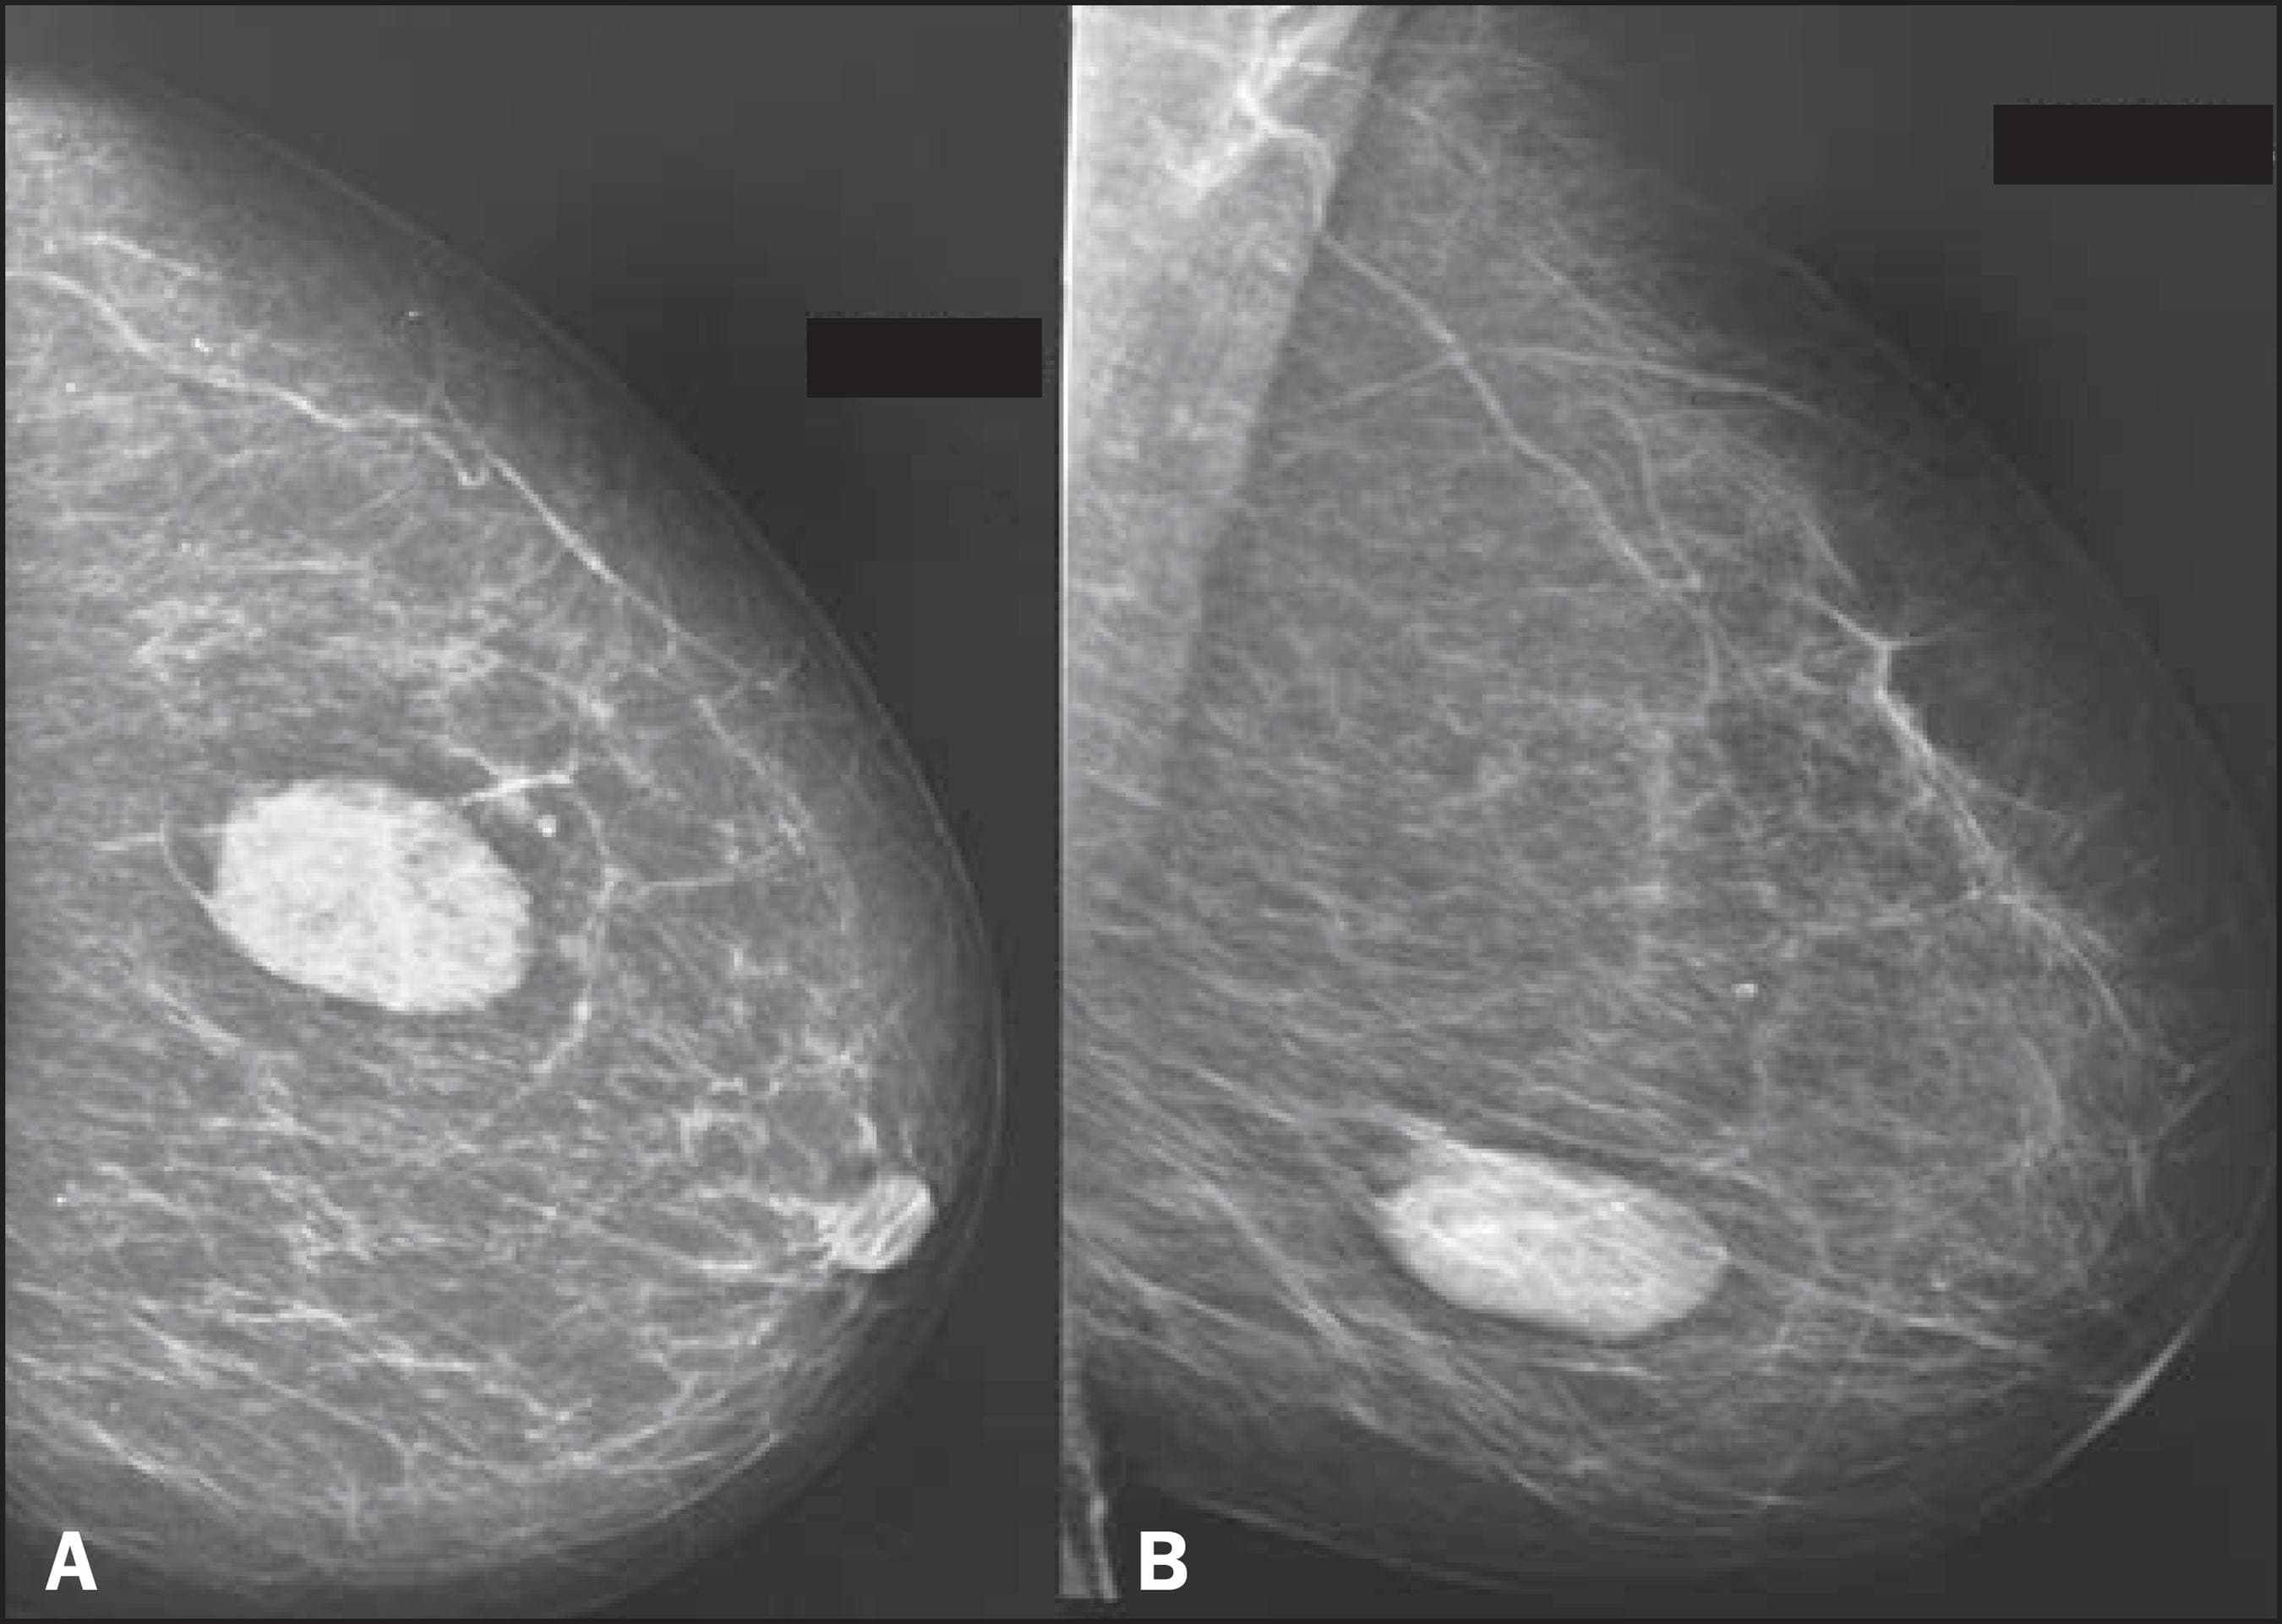

Фото раковой шишки на теле

Раковые шишки могут возникать не только на лице, но и на других частях тела. На фотографиях вы можете увидеть примеры раковых шишек на шее, руках, ногах и туловище. Обратите внимание на различные формы и размеры раковых шишек, а также на их внешний вид.